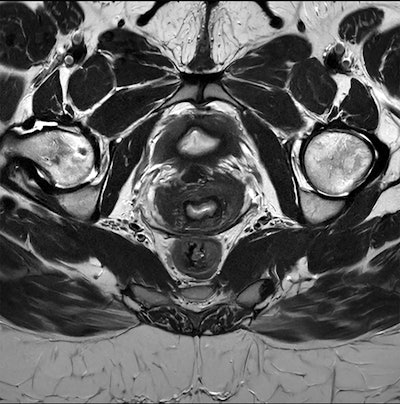

Clinical pelvis image acquired on a Ingenia Evolution 3-tesla scanner and reconstructed using Philips' SmartSpeed Precise AI-based image reconstruction technology. Image courtesy of Philips.

In MRI, the vendor unveiled SmartSpeed Precise, a new work-in-progress, dual AI-image reconstruction package that enables scans to be conducted three times faster than with the firm’s previous SENSE reconstruction technology. With SmartSpeed Precise, the company’s Adaptive CS-Net algorithm removes noise from images acquired via accelerated protocols. Next, the company’s new Precise Image Net AI model removes artifacts and sharpens the images. The result is an 80% improvement in image sharpness, according to the vendor.

When released, SmartSpeed Precise will be available across the company’s 1.5-tesla and 3-tesla MRI scanners, with the exception of Prodiva 1.5T and Multiva 1.5T, Philips said. Philips hopes to receive the CE Mark for SmartSpeed Precise by the end of the year.